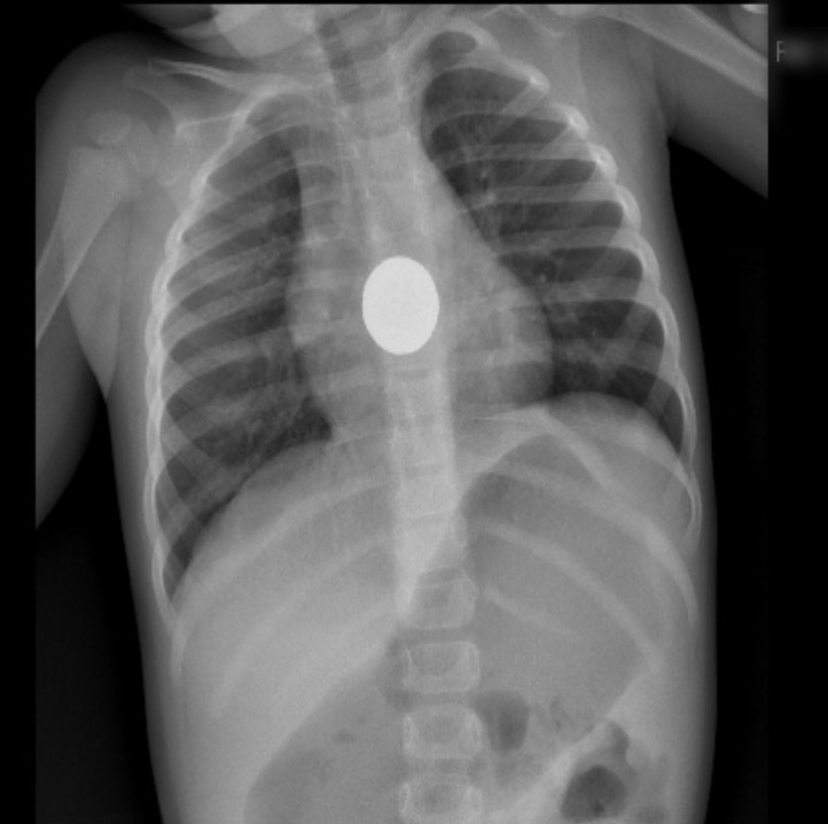

Guanajuato, Guanajuato. 23 de mayo 2023. -La Dra. Verónica Álvarez Elorza, Médico- Pediatra adscrita a la unidad del Hospital Materno Infantil en Irapuato informó acerca de la broncoaspiración que es el paso accidental de alimentos sólidos o líquidos a las vías respiratorias.

Es una urgencia médica que pone en peligro la vida del infante, por eso es importante que los papás sepan que hacer ante un episodio de broncoaspiración.